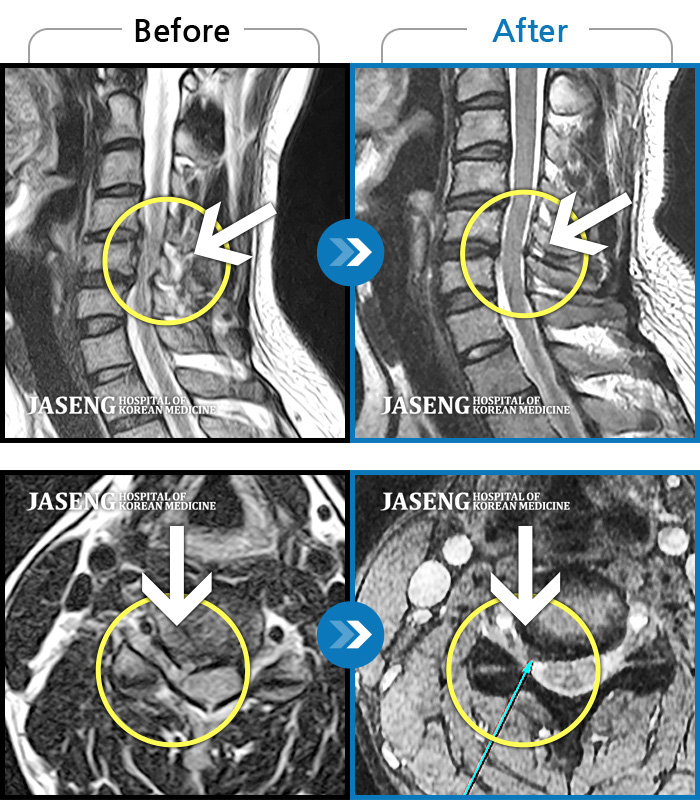

Before

After

2-3년간 디스크로 허리통증과 하지방사통으로 여러 치료하였으나 나아지지 않는 증상

2024.10.09 ~ 2025.03.22